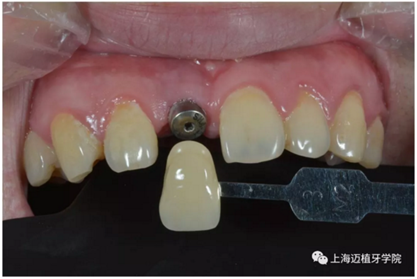

比色:3/M2

氧化鋯個(gè)性基臺

口內(nèi)個(gè)性化基臺:

戴牙 最終修復(fù)效果